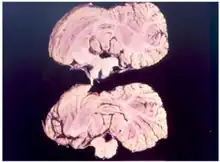

Diagnosis

Kuru is diagnosed by reviewing the patient's history of cerebellar signs and symptoms, performing neurological exams, and excluding other neurological diseases during exams.[15] The symptoms evaluated are typically coordination issues and involuntary muscle movements, but these markers can be confused with other diseases that affect the nervous and muscle system; physical scans are often required to differentiate Kuru from other disorders.[26][27] There is no laboratory test to determine the presence of Kuru, except for postmortem evaluation of central nervous system (CNS) tissues, so diagnoses are achieved by eliminating other possible disorders.